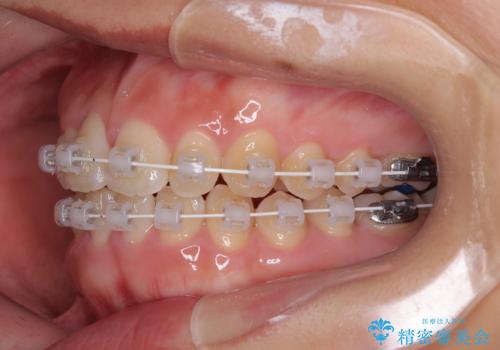

- 矯正装置

- 審美装置

- 治療期間

- 1年1ヶ月

治療計画

・アーチを側方に拡大して歯が並ぶスペースを確保

・抜歯は避け、非抜歯での対応

・目立ちにくい審美装置による矯正

・治療期間をできるだけ短縮するために、綿密な装置管理と協力体制を構築